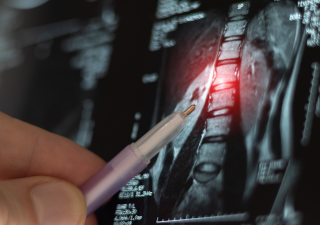

MEDICAL NEGLIGENCE

CLAIMS

Our specialist Clinical & Medical Negligence solicitors can help if you've suffered as a result of medical negligence or malpractice & can provide you with advice and a free initial consultation about making a No Win No Fee claim.